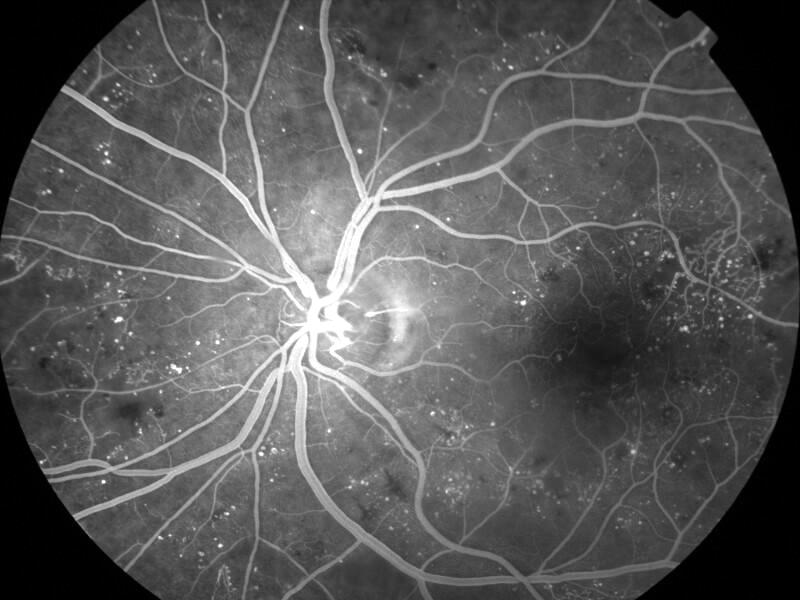

rétinopathie diabétique pré-proliférante